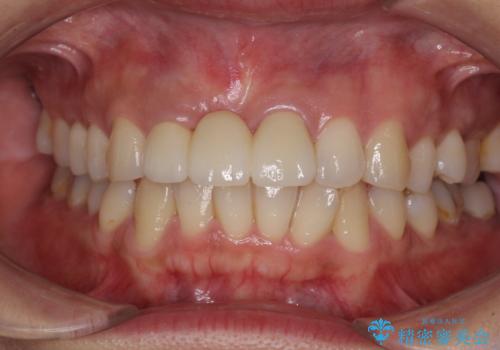

治療途中で放置した前歯 オールセラミックブリッジ

抜歯後は歯肉が痩せてしまうため、歯肉移植を行って歯肉の形態を改善した後、オールセラミックブリッジにて補綴することとしました。

歯肉移植により歯肉ラインや歯の形態を整えることができ、ブリッジによる補綴としたことで舞えば全体の色調を整えることができました。